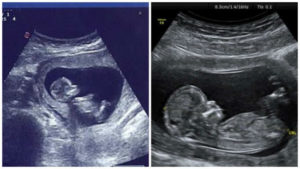

Ультразвуковое исследование – наиболее информативный и безопасный метод, который позволяет отслеживать течение беременности и вовремя определить развитие патологий. Обязательное УЗИ назначается беременным на сроке около 11-13 недель. Многих будущих матерей на этом сроке интересует вопрос, можно ли на первом скрининге узнать пол ребенка.

Ультразвуковое исследование помогает узнать точный срок беременности (он может отличаться от срока, рассчитанного по дате последней менструации). На первом УЗИ-скрининге замеряют параметры плода: размеры головы, длину костей рук и ног, оценивают работу сердца, количество амниотической жидкости, состояние плаценты и другие важные показатели протекания беременности.

Пол ребенка закладывается при зачатии, но до 7 недели эмбрион не имеет каких-либо явных половых признаков. На этом сроке образуется половой бугорок, из которого позже под действием гормонов сформируются женские либо мужские органы.

До 9 недели внешне половые органы будущего мальчика или девочки выглядят идентично.

После 10 недели, когда эмбрион уже становится зародышем, опытный врач может предположить пол будущего ребенка с высокой долей вероятности, но только по расположению полового бугорка, так как визуально половые органы по-прежнему практически не отличаются.

Считается возможным определение пола по результатам ультразвукового исследования примерно с 12 недели беременности, но такое предположение может быть неточным и зависит от нескольких факторов: